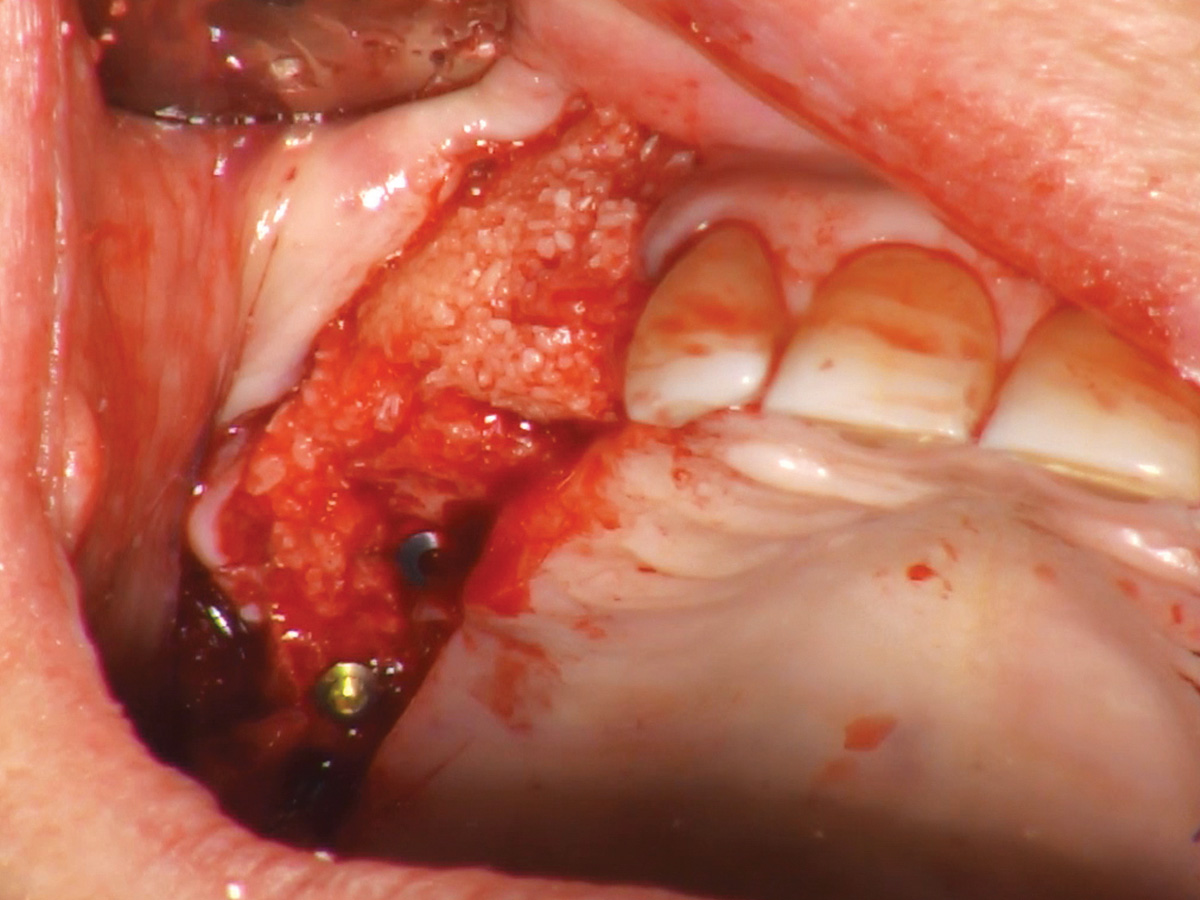

Abbildung 3

Augmentation des Sinusbodens mit OsteoBiol® GTO®.